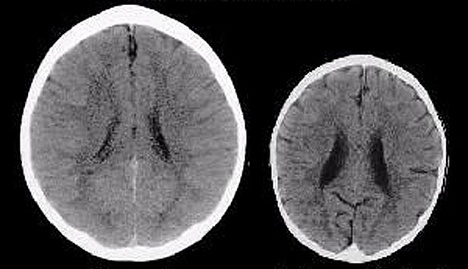

What’s the difference between these two brains? asks The Telegraph. “The primary cause of the extraordinary difference between the brains of these two three-year-old children,” says the journalist, “is the way they were treated by their mothers.”

According to the paper “The child with the much more fully developed brain was cherished by its mother, who was constantly and fully responsive to her baby. The child with the shrivelled brain was neglected and abused.”

Firstly, it’s worth saying that reduced brain size is clearly related to neglect and abuse but the images are not a typical representation of this.

These scans were originally published in an article on child abuse by neuroscientist Bruce Perry who drew them from an unpublished abstract [pdf] of a study on neglect in children, which didn’t control for malnutrition or drug exposure during pregnancy.

They’re described as showing CT scans of three-year-olds, one normal and the other neglected who has a head size smaller 97% of children his or her age. This would make him or her almost diagnosable with microcephaly, a neurological disorder of small head size usually caused by a genetic defect.

In other words, unless you include ‘starvation’ under the concept or ‘poor interaction with the mother’ the scans really don’t represent what typically happens to children who are emotionally neglected.